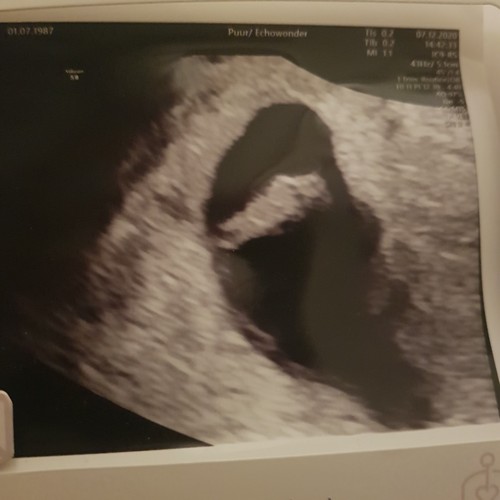

Ik dacht 8 weken te zijn bij de echo ze hadden me alleen iets terug gezet naar 7+4. Nu alweer een goede termijn echo gehad en vandaag alweer 11+4.

Helaas moeilijk tezien gisteren echo gehad ban 8+5 maar mijn baarmoeder ligt nog wat verder naar achter dus niet zn hele helderen echo maar hartje klopt en alles was goed 😍😍